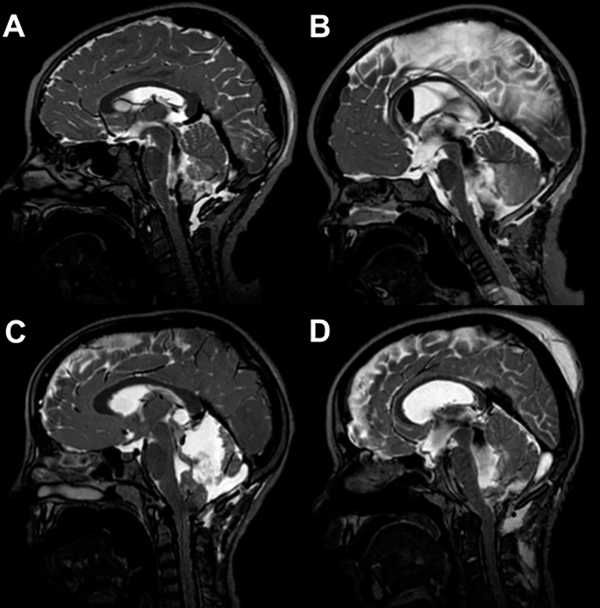

La obstrucción de salida del IV ventrículo se interpretó como la ausencia de comunicación de LCR (permeabilidad) en imágenes de RMI entre el IV ventrículo y la cisterna magna (Figura 2).

Figura 2: Imágenes de RM sagitales ponderadas en T2 drive, de cuatro postoperatorios de resección tumoral de fosa posterior. En A y B se evidencia vacío de flujo entre IV ventrículo y cisterna magna. En C y D se observa la ausencia de comunicación de LCR (permeabilidad) entre IV ventrículo y cisterna magna.